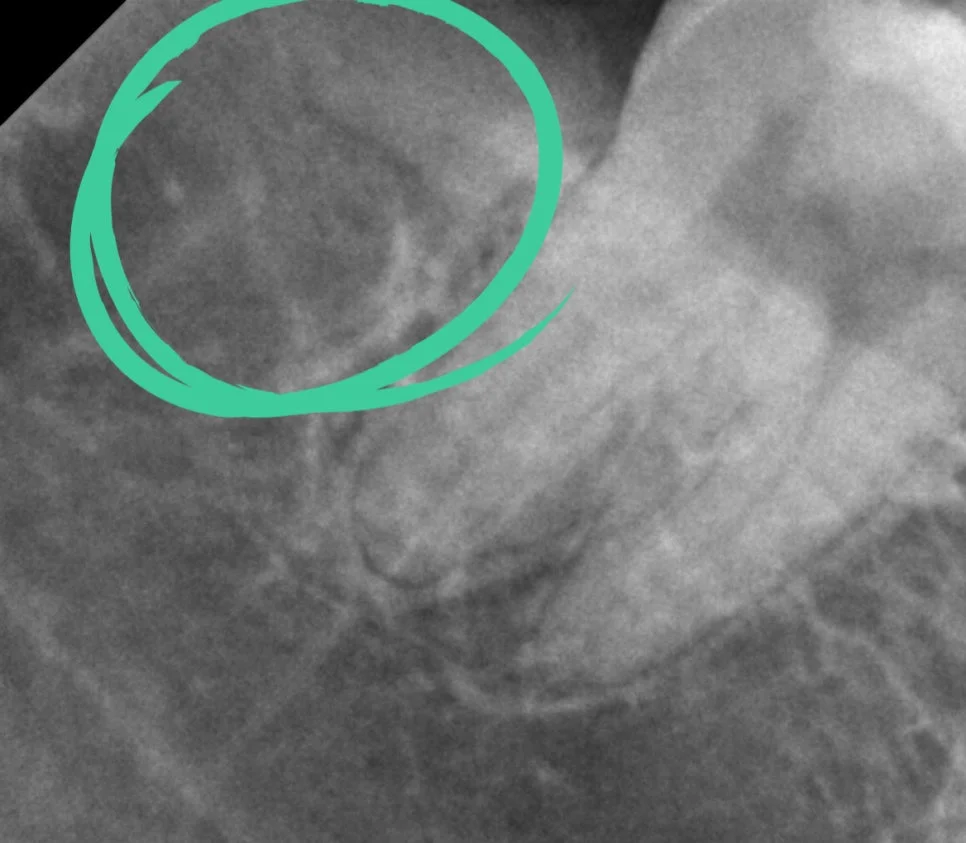

케이스2 우측 매복 사랑니 제2대구치 위협

우측 하악 매복 사랑니 — 제2대구치 바깥 면을 위협하는 가장 고난도 케이스

오른쪽 아래 매복 사랑니는 제2대구치의 바깥 면을 위협하고 있어 가장 난도가 높지만 빠르게 발치를 해줘야 하는 상태입니다.